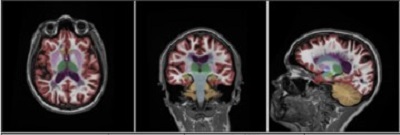

Neuro Quant

Automated brain image analysis solutions

Automatically segments and measures volumes of brain structures and compares these volumes to a normative database adjusted for age, gender and intracranial volume.